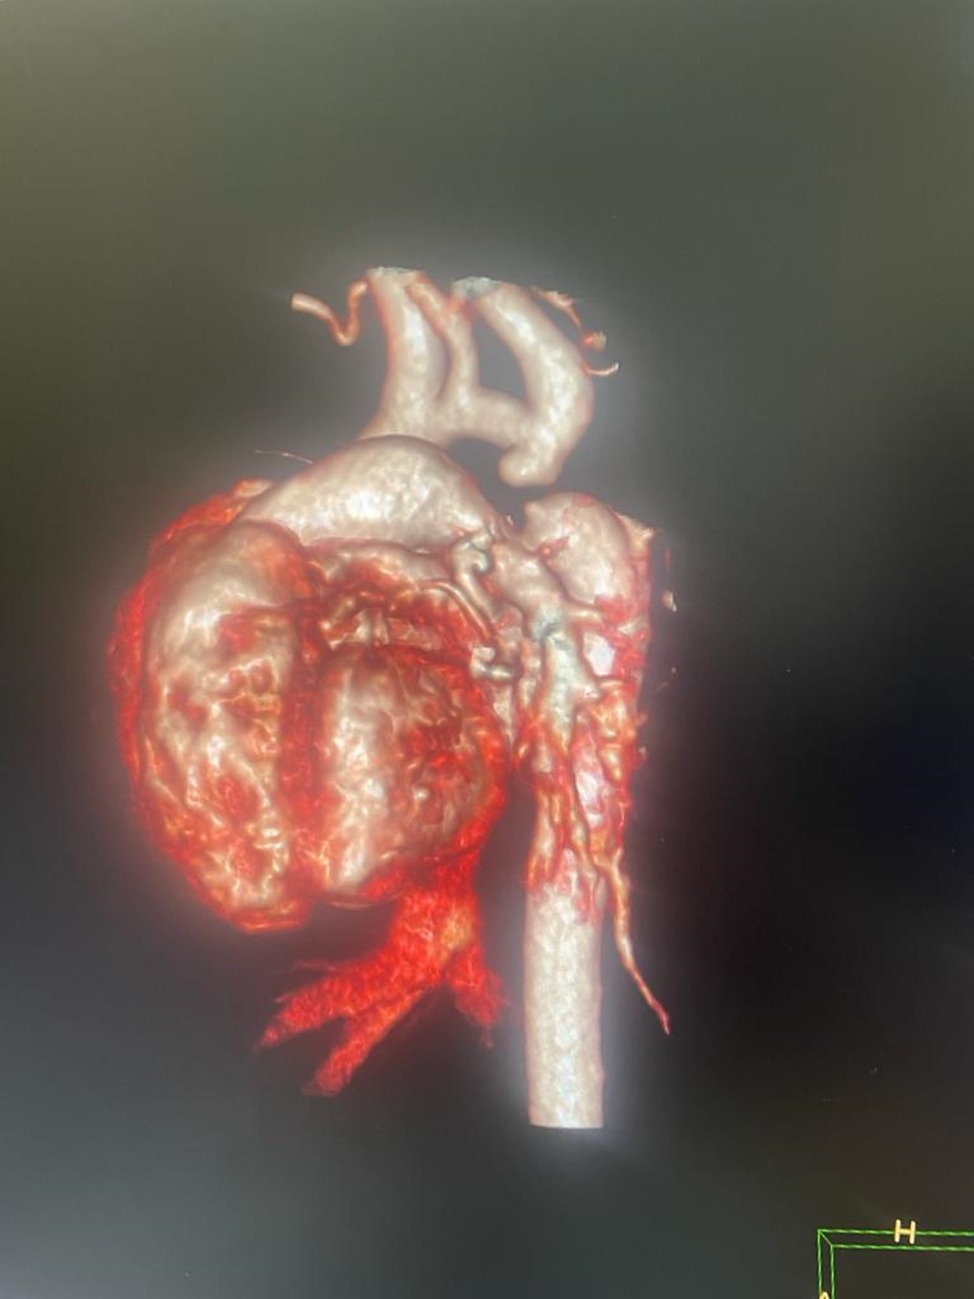

Впервые в Таразе 8-дневному новорожденному с критическим врожденным пороком сердца сделали экстренную операцию в Научно-клиническом центре кардиохирургии и трансплантологии (НКЦКТ) с диагнозом Критическая коарктация аорты. Новорожденный Г. в возрасте 8 дней, из города Тараз, поступил в НКЦКТ в крайне тяжелом состоянии, с жалобами на выраженную одышку в покое с ЧД 80 в минуту, синюшность кожных покровов, отсутствие мочи, сатурация кислорода 60%. Со слов мамы о пороке стало известно на втором триместре обследования УЗИ скрининг плода. В роддоме ОПЦ был выставлен предварительный диагноз ВПС Коарктация аорты. На 8 день жизни, учитывая критические жалобы обратились в городскую детскую больницу, оттуда направлен в НКЦКТ, где специалистами Центра проведено ЭХОКГ, КТ с контрастированием, диагноз подтвержден: Критическая коарктация аорты. Решением консилиума, в составе зав. детским кардиохирургическим отделением Мухамедовым Икромом, зав. реанимации Розбаевым Зафаром и детским кардиологом Уколовой Юлией, в 5 утра 8.10.2023 г. была выполнена по жизненным показаниям экстренная операция: резекция критической коарктации аорты с наложением протяженного анастомоза в «конец в конец».